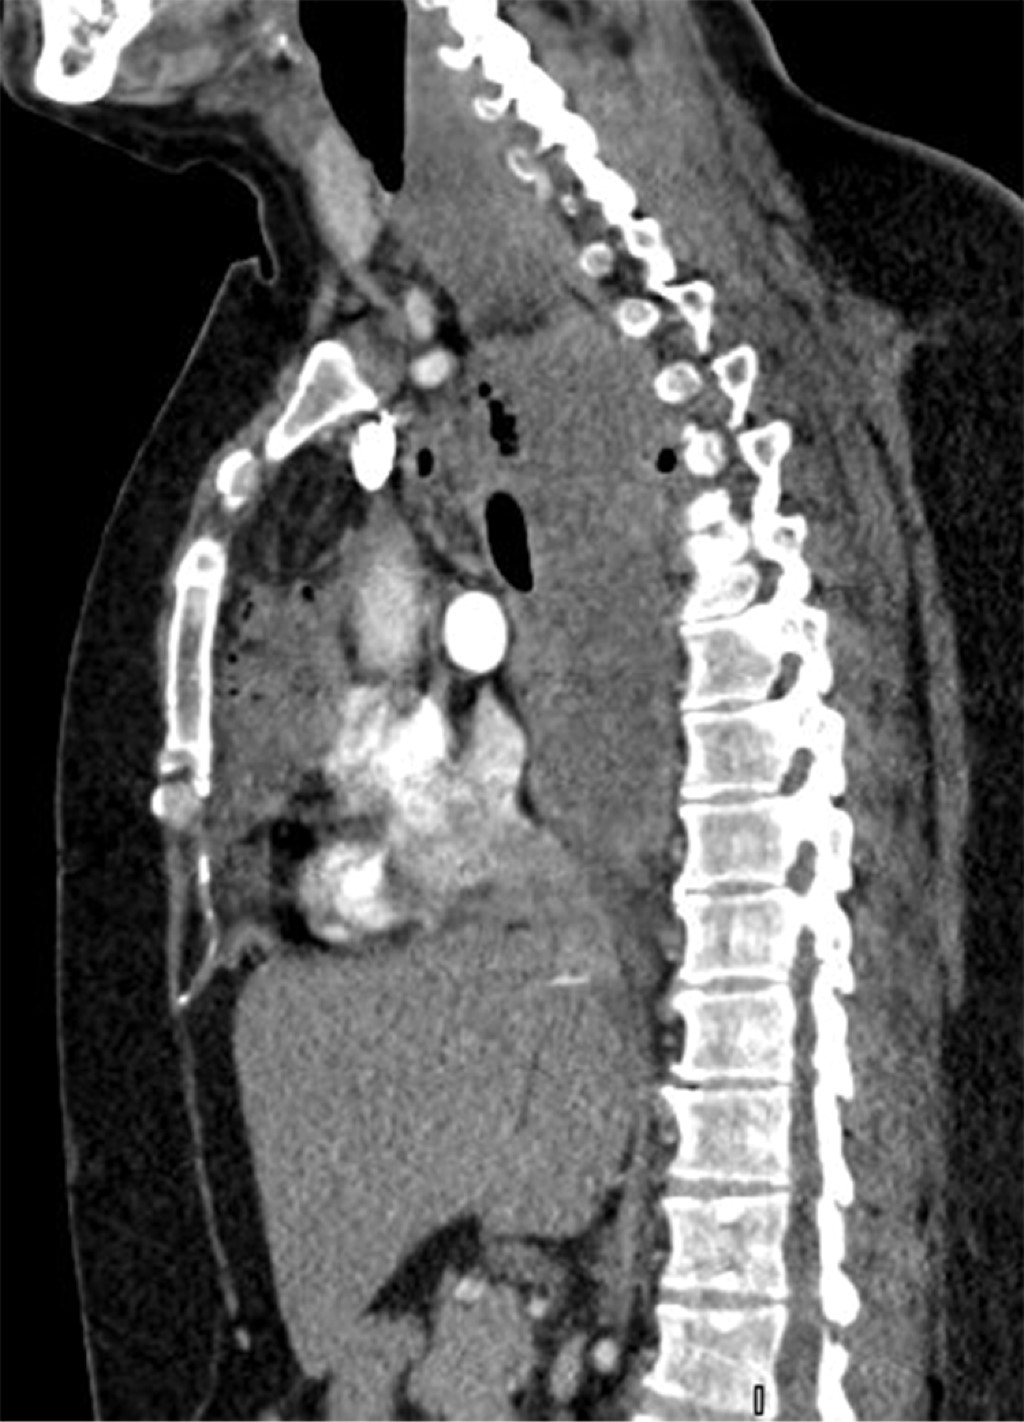

El papel de los estudios de imagen es de vital importancia en el diagnóstico, sin dejar de lado la historia clínica minuciosa y la exploración física. Los principales hallazgos en la radiografía de tórax simple establecen la sospecha de MND junto con los signos y síntomas clínicos de infección severa asociados a la presencia del antecedente de infección cervical, dental u orofaríngea. Dichos hallazgos radiológicos pueden ser: ensanchamiento del mediastino, neumomediastino, niveles hidroaéreos mediastinales, desplazamiento anterior de la columna de aire traqueal por una opacidad prevertebral de los tejidos blandos, agrandamiento de la silueta cardíaca y pérdida de la lordosis normal de la columna cervical así como derrame pleural unilateral o bilateral.9,10,12 De forma inmediata deberá realizarse una tomografía computarizada (TC) cervicotorácica, ya que la TC de tórax y cuello puede revelar información detallada con respecto al alcance del proceso de necrosis, y sugiere, dentro del marco del enfoque de tratamiento quirúrgico, el mejor abordaje para un drenaje efectivo con la finalidad de optimizar el mejor resultado posquirúrgico para el paciente y con ello la necesidad de menos reintervenciones.9,10,13-17

En nuestra serie la radiografía de tórax sigue siendo el estudio inicial en todo paciente con problema respiratorio por su accesibilidad y rápido resultado (Figura 1); sin embargo, la tomografía de tórax sigue siendo el estándar de oro en nuestra institución para el diagnóstico y planeación de manejo quirúrgico en los pacientes con mediastinitis (Figura 2).